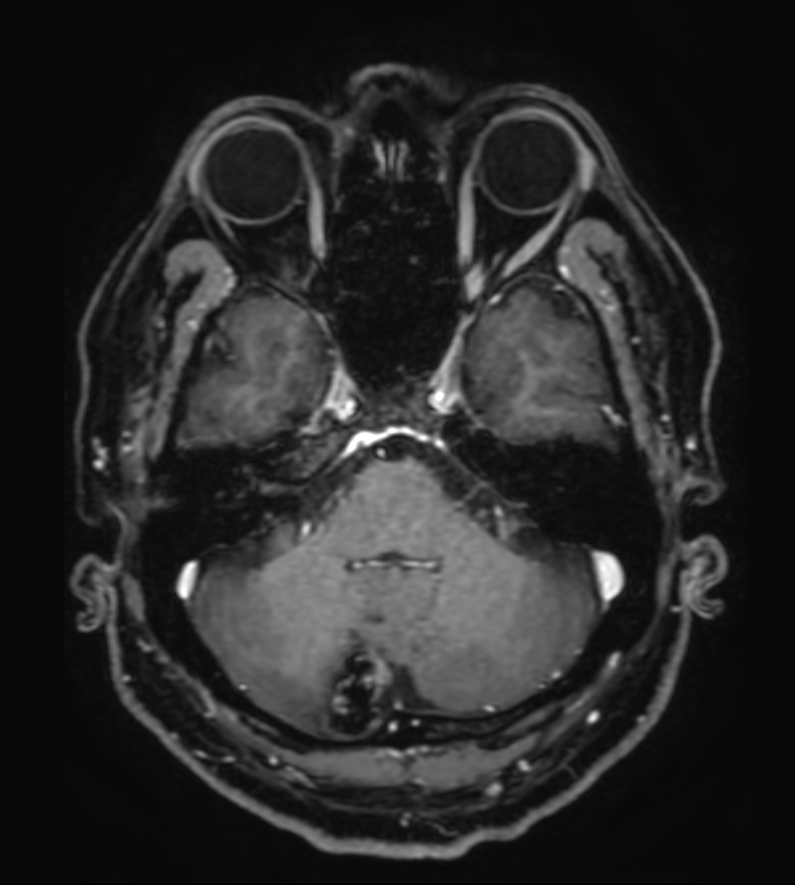

T1w FFE Compressed SENSE

T1w FFE post-gado Compressed SENSE

3D T1w FFE FatSat post-gado Compressed SENSE